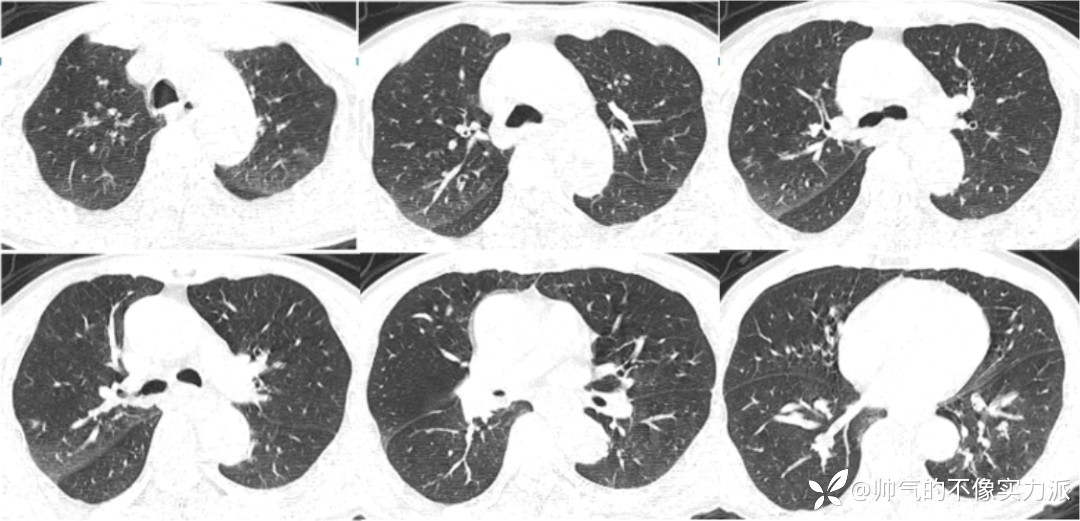

急诊胸部CT

2020年12月7日,急诊胸部CT提示肺部慢性炎症,右肺小结节影(图1)。

图1 患者胸部CT(2020-12-07)